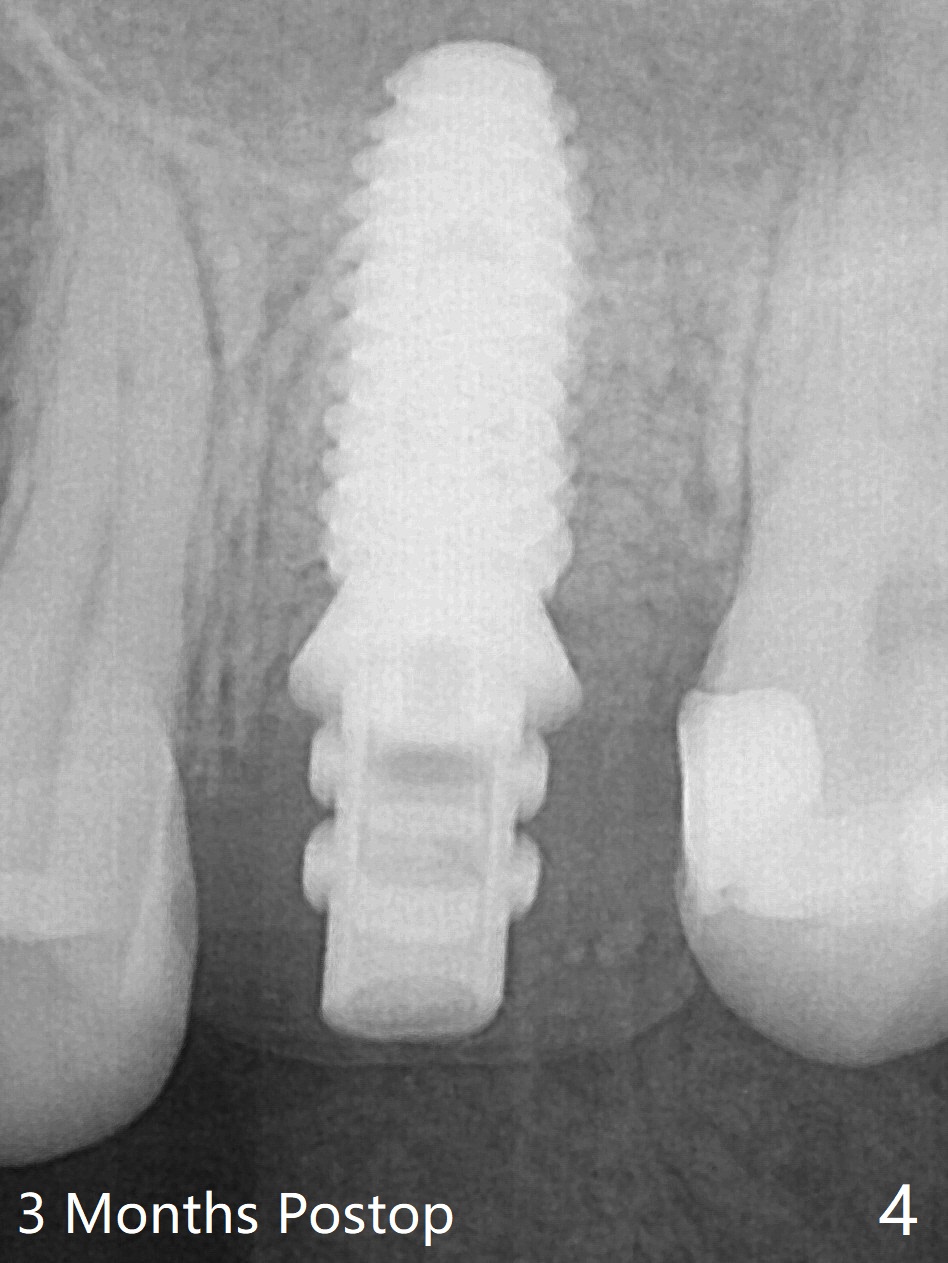

When a 4.5x10 mm implant is placed with sinus lift at #14 (Fig.1), a 5.2x8(2) mm temporary abutment is inserted with height adjustment. Advantage is that an immediate provisional (Fig.2 yellow lines; Fig.3 P) has an ideal emergency profile so that there is less chance of food impaction associated with the future permanent crown. It appears that the mesial portion of bone graft in the mesial gap has been converted to the native bone (lamellar) in 3 months (Fig.4). Bone graft appears to be integrated to the native bone and the implant 14 months postop (Fig.5).